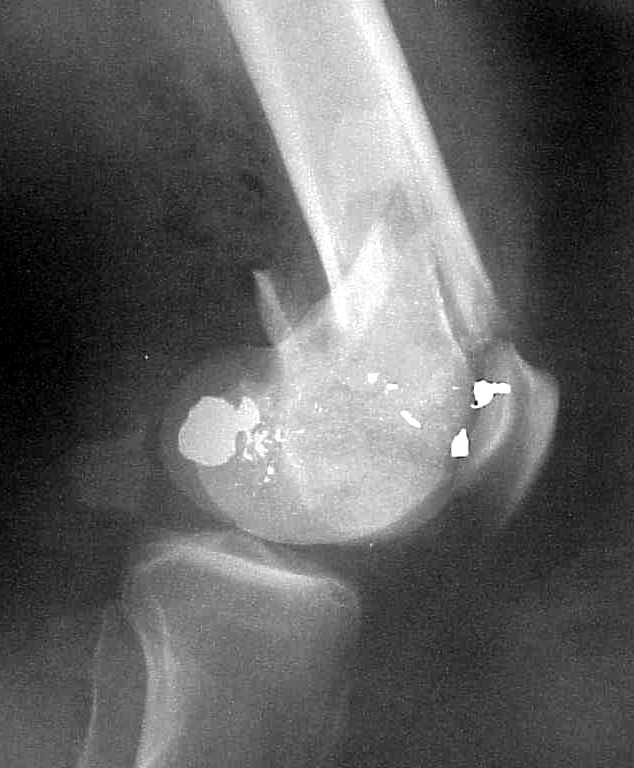

A CT and knee xrays would help identify lateral condyle comminution and/or a "hoffa fragment" of the posterior condyle. I am concerned that the lateral cortex is not sufficient to give purchase for a retrograde IMN. blocking screws could improve this as a possibility. A long blade or LISS if avaible would be my secondary choices. Good luck. Any chance you can get these cases transferred earlier when it

Lateral condyle looks too small for the blade, and the plate too short.

Use 6.5 mm cannulated screws if you have and

place one anterior to where IMN will go if anterior cortex if insufficient and AP screws on either side of the IMN out of the trochlea to provide some additional varus/valgus stability. I worry about the leg going into valgus w/the lack of lateral cortex.

See attached case that was done several years ago before LISS. He had comminuted trochlea and anterior blocking screws were used to prevent anterior IMN cut-out.